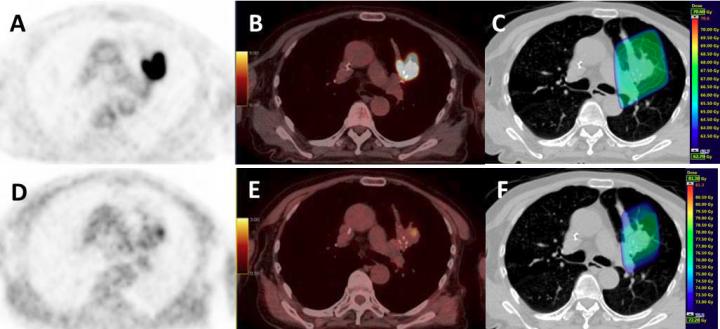

RESTON, Va. - Fluorine-18 ( 18 F)-fluoromisonidazole (FMISO) is a positron emission tomography (PET) radiotracer that is widely used to diagnose hypoxia (insufficient oxygen supply to tissue), and non-small cell lung cancer (NSCLC) patients with FMISO uptake are known to face a poor prognosis. A multicenter French Phase II study featured in the July issue of The Journal of Nuclear Medicine (JNM) investigated whether a selective radiotherapy (RT) dose increase to tumor areas with significant FMISO uptake in NSCLC patients could improve outcomes.

The study, conducted by 15 academic PET facilities across France, evaluated 54 patients with localized, advanced non-small cell cancers, who were undergoing chemoradiotherapy. For each patient, two FDG-PET/CT and two FMISO-PET/CT scans were performed using the same machine and under the identical operational conditions. Quality control was centrally supervised to secure homogeneity in the image quality in all participating centers. In 24 of the patients, the radiotherapy dose could be increased up to 86 Gy on hypoxic areas identified on FMISO PET/CT. Unfortunately, this dose increase did not improve patient outcomes.